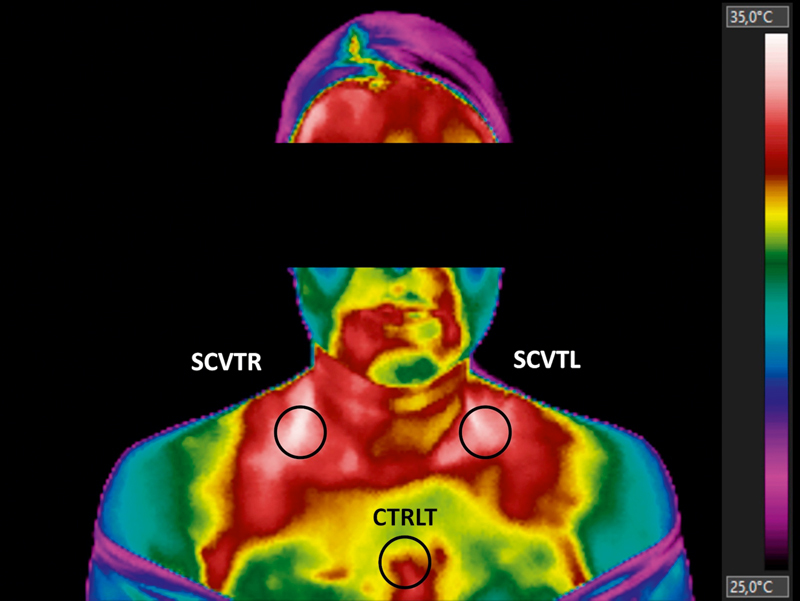

Brown adipose tissue (BAT) helps control body weight and is inversely correlated with body fat, but it is unclear whether it is subcutaneous adipose tissue (SAT) or visceral adipose tissue (VAT) that is related to BAT activation. The presented study aimed to verify the relation of SAT and VAT on BAT activation through infrared thermography (IRT) and cold stimulation in adult women. Forty women were evaluated in body composition and skin temperature (Tskin) acquisition by IRT. Student's independent t-test, Pearson's correlation, and two-way repeated measures ANOVA with Tukey post-hoc were applied. Women with low amounts of SAT and VAT had a significant increase in supraclavicular Tskin (SCVT). Medium negative degrees of linear variation were found before and after cold stimulation between SCVT, SAT and VAT. A significant effect of the moment factor and the group factor on the SCVT between subjects divided into the groups were pointed out. No difference was found in the relation between SAT, VAT, and BAT in adult women, pointing out that both types of fat are equally related. These results can help clinical practice understand clearly, through IRT, that the high accumulation of SAT and VAT can impair the activation of BAT and hinder the loss of weight in women.